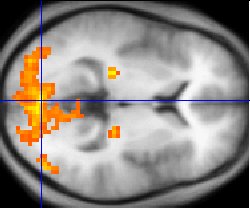

Sample fMRI data

This example of fMRI data shows regions of activation including primary visual cortex (V1, BA17), extrastriate visual cortex and lateral geniculate body in a comparison between a task involving a complex moving visual stimulus and rest condition (viewing a black screen). The activations (yellow-red) are shown (as is typical) against a background based on the average structural images from the subjects in the experiment.